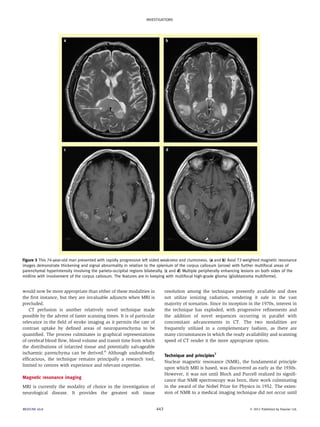

Figure 3 This 74-year-old man presented with rapidly progressive left sided weakness and clumsiness. (a and b) Axial T2-weighted magnetic resonance

images demonstrate thickening and signal abnormality in relation to the splenium of the corpus callosum (arrow) with further multifocal areas of

parenchymal hyperintensity involving the parieto-occipital regions bilaterally. (c and d) Multiple peripherally enhancing lesions on both sides of the

midline with involvement of the corpus callosum. The features are in keeping with multifocal high-grade glioma (glioblastoma multiforme).